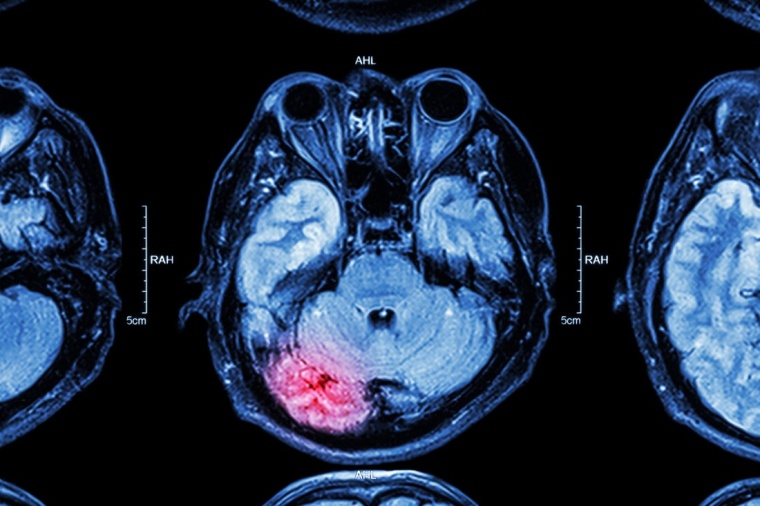

Schlaganfälle können verschiedene Ursachen haben, in den meisten Fällen handelt es sich um sogenannte ischämische Schlaganfälle, also eine Unterbrechung der Durchblutung eines Gehirnareals. Ursächlich sind oft Verschlüsse von Hirnarterien durch Arteriosklerose und/oder Blutgerinnsel z.B. aus dem Herzen. Aber auch Partikel von arteriosklerotischen Plaques* der Halsschlagadern (Arteria carotis), die mit dem Blut mitgerissen werden, können einen Schlaganfall auslösen. Mit Zunahme der Plaques bzw. fortschreitender Gefäßverengung (Stenosierung) der A. carotis interna steigt auch das Schlaganfallrisiko. Als Symptom einer Carotisstenose bzw. als Vorzeichen eines drohenden Schlaganfalls kann es zu einer sogenannten TIA (transitorischen ischämischen Attacke) kommen – diese geht mit Schlaganfallsymptomen, z. B. Sehstörungen oder Lähmungen einher, die jedoch nur kurzzeitig anhalten (Minuten bis maximal wenige Stunden) und sich dann wieder zurückbilden. Eine asymptomatische Carotisstenose ist dagegen ein Zufallsbefund. Auch Stenosen mit Einengungen von weit über 50% können asymptomatisch sein und werden meist im Rahmen eines Gefäßscreenings entdeckt. Hochgradige asymptomatische Carotisstenosen können das Schlaganfallrisiko erhöhen und behandelt werden.